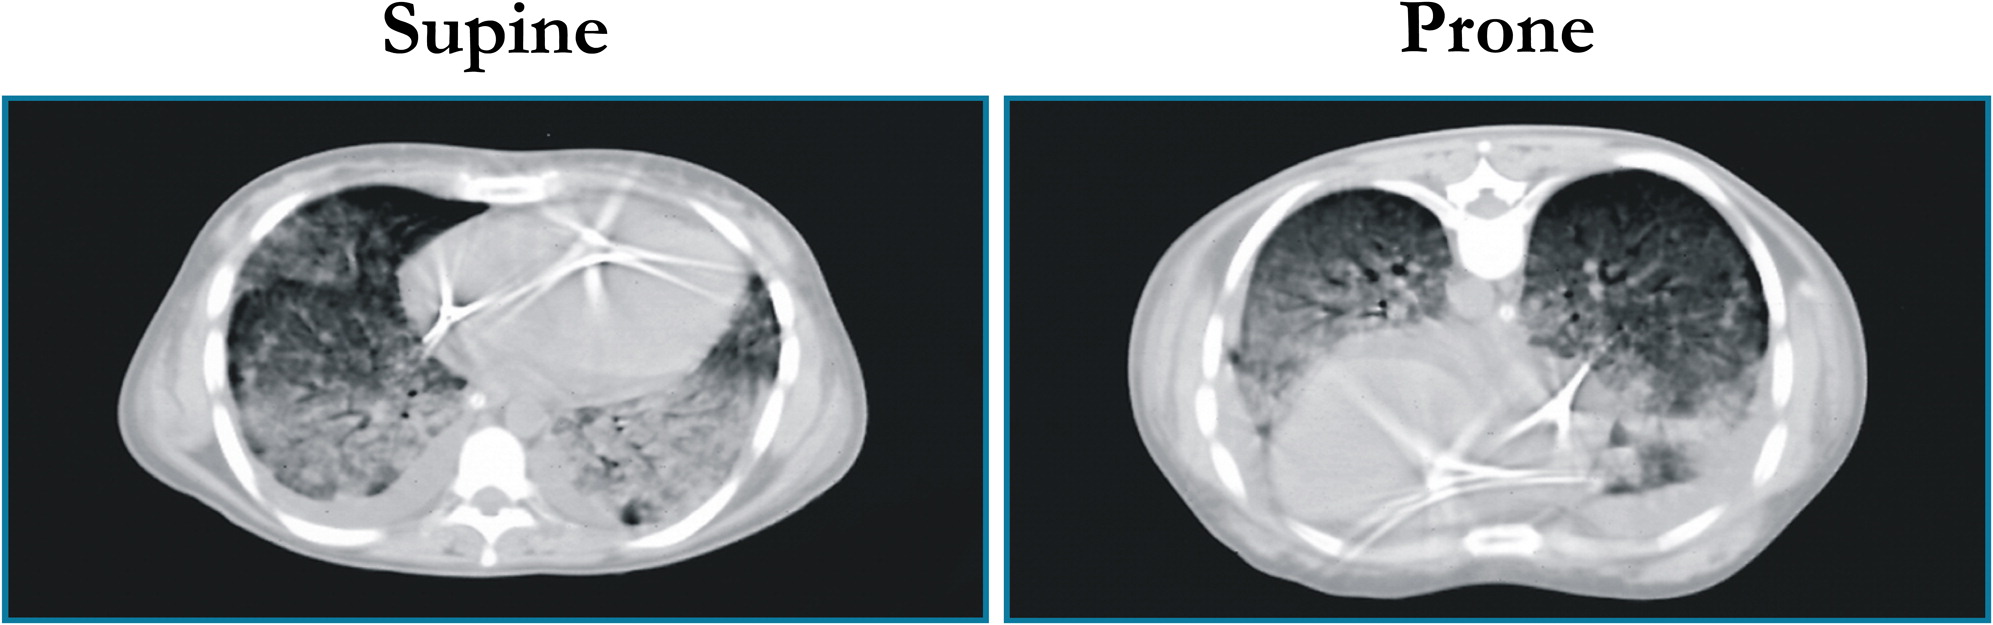

Osservando le TC polmonari dei pazienti con insufficienza respiratoria acuta in posizione supina, noi vedevamo che tutte le lesioni erano sostanzialmente dipendenti, cioè nelle zone del polmone più vicine alle vertebre, mentre in alto, verso lo sterno, il polmone non sembrava tanto compromesso. La sola radiografia, invece, ci diceva che era coinvolto tutto il polmone. Allora la cosa più naturale ci sembrò quella di mettere i pazienti a pancia in giù. Notammo che l’ossigenazione saliva. Perché saliva l’ossigenazione?

Noi pensavamo che l’aumento dell’ossigenazione fosse motivato dallo spostamento di flusso in quella parte di polmone con minori densità osservabili alla TC, quello che noi abbiamo chiamato baby lung. Sottoponendo i pazienti in posizione prona a TC fummo sorpresi nel vedere un aumento di densità verso lo sterno. Nacque così il modello, ancora valido, del polmone assimilabile ad una spugna.

Si immagini una spugna asciutta, che ha pori di una certa dimensione. Immaginiamo quindi di mettere questa spugna nell’acqua. Togliamola dall’acqua e osserviamola appoggiata sul bordo della vasca da bagno. Si vedrà che i pori in basso diminuiscono di volume perchè sono schiacciati dal peso della spugna sovrastante. Mettendo il paziente in posizione prona, è come se il polmone/spugna obbligasse l’aria ad uscire dalle parti posteriori. Liberando le parti posteriori del polmone prima schiacciate e comprimendo un po’ quelle anteriori, siccome la perfusione rimane invece uniforme, a differenza di quanto pensavamo in precedenza, allora in questo modo si ha una porzione maggiore di polmone “aperto”, cosa che fa aumentare l’ossigenazione. Questo è il meccanismo principale, poi esistono altri 2-3 meccanismi minori.

Una tomografia computerizzata rappresentativa di un paziente con ARDS

in posizione supina (a sinistra) e in posizione prona (a destra)

I pazienti affetti da COVID-19 in fase iniziale non presentano edema, ossia un polmone che somiglia ad una grossa spugna piena d’acqua. In fase iniziale si ha un rapporto ventilazione/perfusione alterato. Allora, mettendo questi pazienti in posizione prona, otteniamo benefici grazie al primo meccanismo che ho descritto. Siccome abbiamo una perfusione che tende ad andare gravitariamente, quando mettiamo i pazienti a pancia in giù, noi mettiamo in condizioni più favorevoli di perfusione la parte non dipendente del polmone, ossia la massa maggiore del polmone che sta verso l’alto. Quindi, con un meccanismo diverso, il risultato finale è lo stesso. Ovviamente se la situazione si aggrava e comincia ad aumentare l’edema, quando il polmone diventa un bello spugnone per intenderci, la posizione prona ci dà benefici attraverso il secondo meccanismo.

Quello che si sta vedendo adesso, anche con la TC, è il corrispettivo di questo. Ci sono due fasi della malattia. In una prima fase pazienti hanno polmoni “L-light” (alta compliance, basso V/Q): in questi pazienti il polmone non pesa tanto quindi non ho l’effetto spugna. In una seconda fase i polmoni diventano “H-heavy” (più simili al quadro di ARDS) e avranno una ridistribuzione delle densità come nell’ARDS classica. I primissimi dati che abbiamo vanno in questa direzione.

Fonte immagine: Gattinoni L, Taccone P, Carlesso E, Marini JJ. Prone position in acute respiratory distress syndrome. Rationale, indications, and limits. Am J Respir Crit Care Med. 2013 Dec 1;188(11):1286-93. doi: 10.1164/rccm.201308-1532CI.